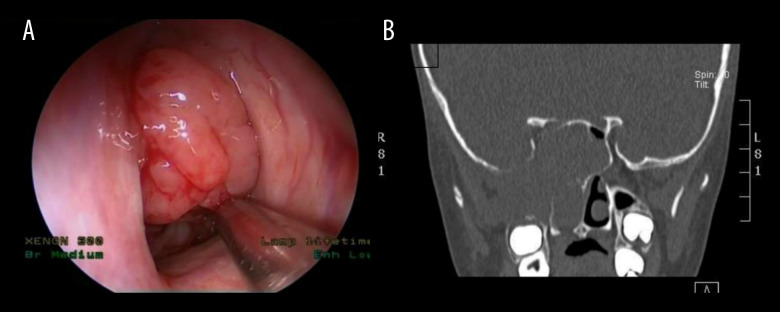

BACKGROUND Pediatric sinonasal tumors are rare, accounting for about 4% of all pediatric head and neck neoplasms. Due to their nonspecific symptoms such as nasal obstruction, epistaxis, and facial pain, these tumors often present diagnostic challenges and lead to delays in managment. Early and accurate diagnosis is crucial to optimize clinical outcomes. CASE REPORT This is a retrospective review of 4 pediatric patients with diagnosis of sinonasal tumors at a tertiary hospital in Saudi Arabia. The series includes 2 benign tumors, osteoma and juvenile nasopharyngeal angiofibroma, and 2 malignant tumors, NK/T-cell lymphoma and rhabdomyosarcoma. Diagnostic workups included nasal endoscopy, CT, MRI, and PET-CT imaging, followed by histopathological confirmation. Benign tumors were successfully treated with image-guided endoscopic excision, with no evidence of recurrence during follow-up periods of 2 and 5 years, respectively, while malignant tumors required a multimodal approach, combining chemotherapy and radiotherapy under multidisciplinary care, and showed stabilization after treatment with continued surveillance. The variety in presentation and complexity of management underscore the diagnostic and therapeutic challenges in this population. CONCLUSIONS This case series highlights the importance of early suspicion, comprehensive imaging, and individualized treatment plans in managing pediatric sinonasal tumors. The use of minimally invasive surgical techniques and preoperative embolization was effective in selected cases. The findings emphasize the role of multidisciplinary collaboration in optimizing outcomes for benign and malignant tumors. Future research should aim to develop standardized diagnostic algorithms and explore advanced diagnostic tools, such as molecular imaging, to facilitate earlier detection and improve treatment precision in pediatric sinonasal oncology.